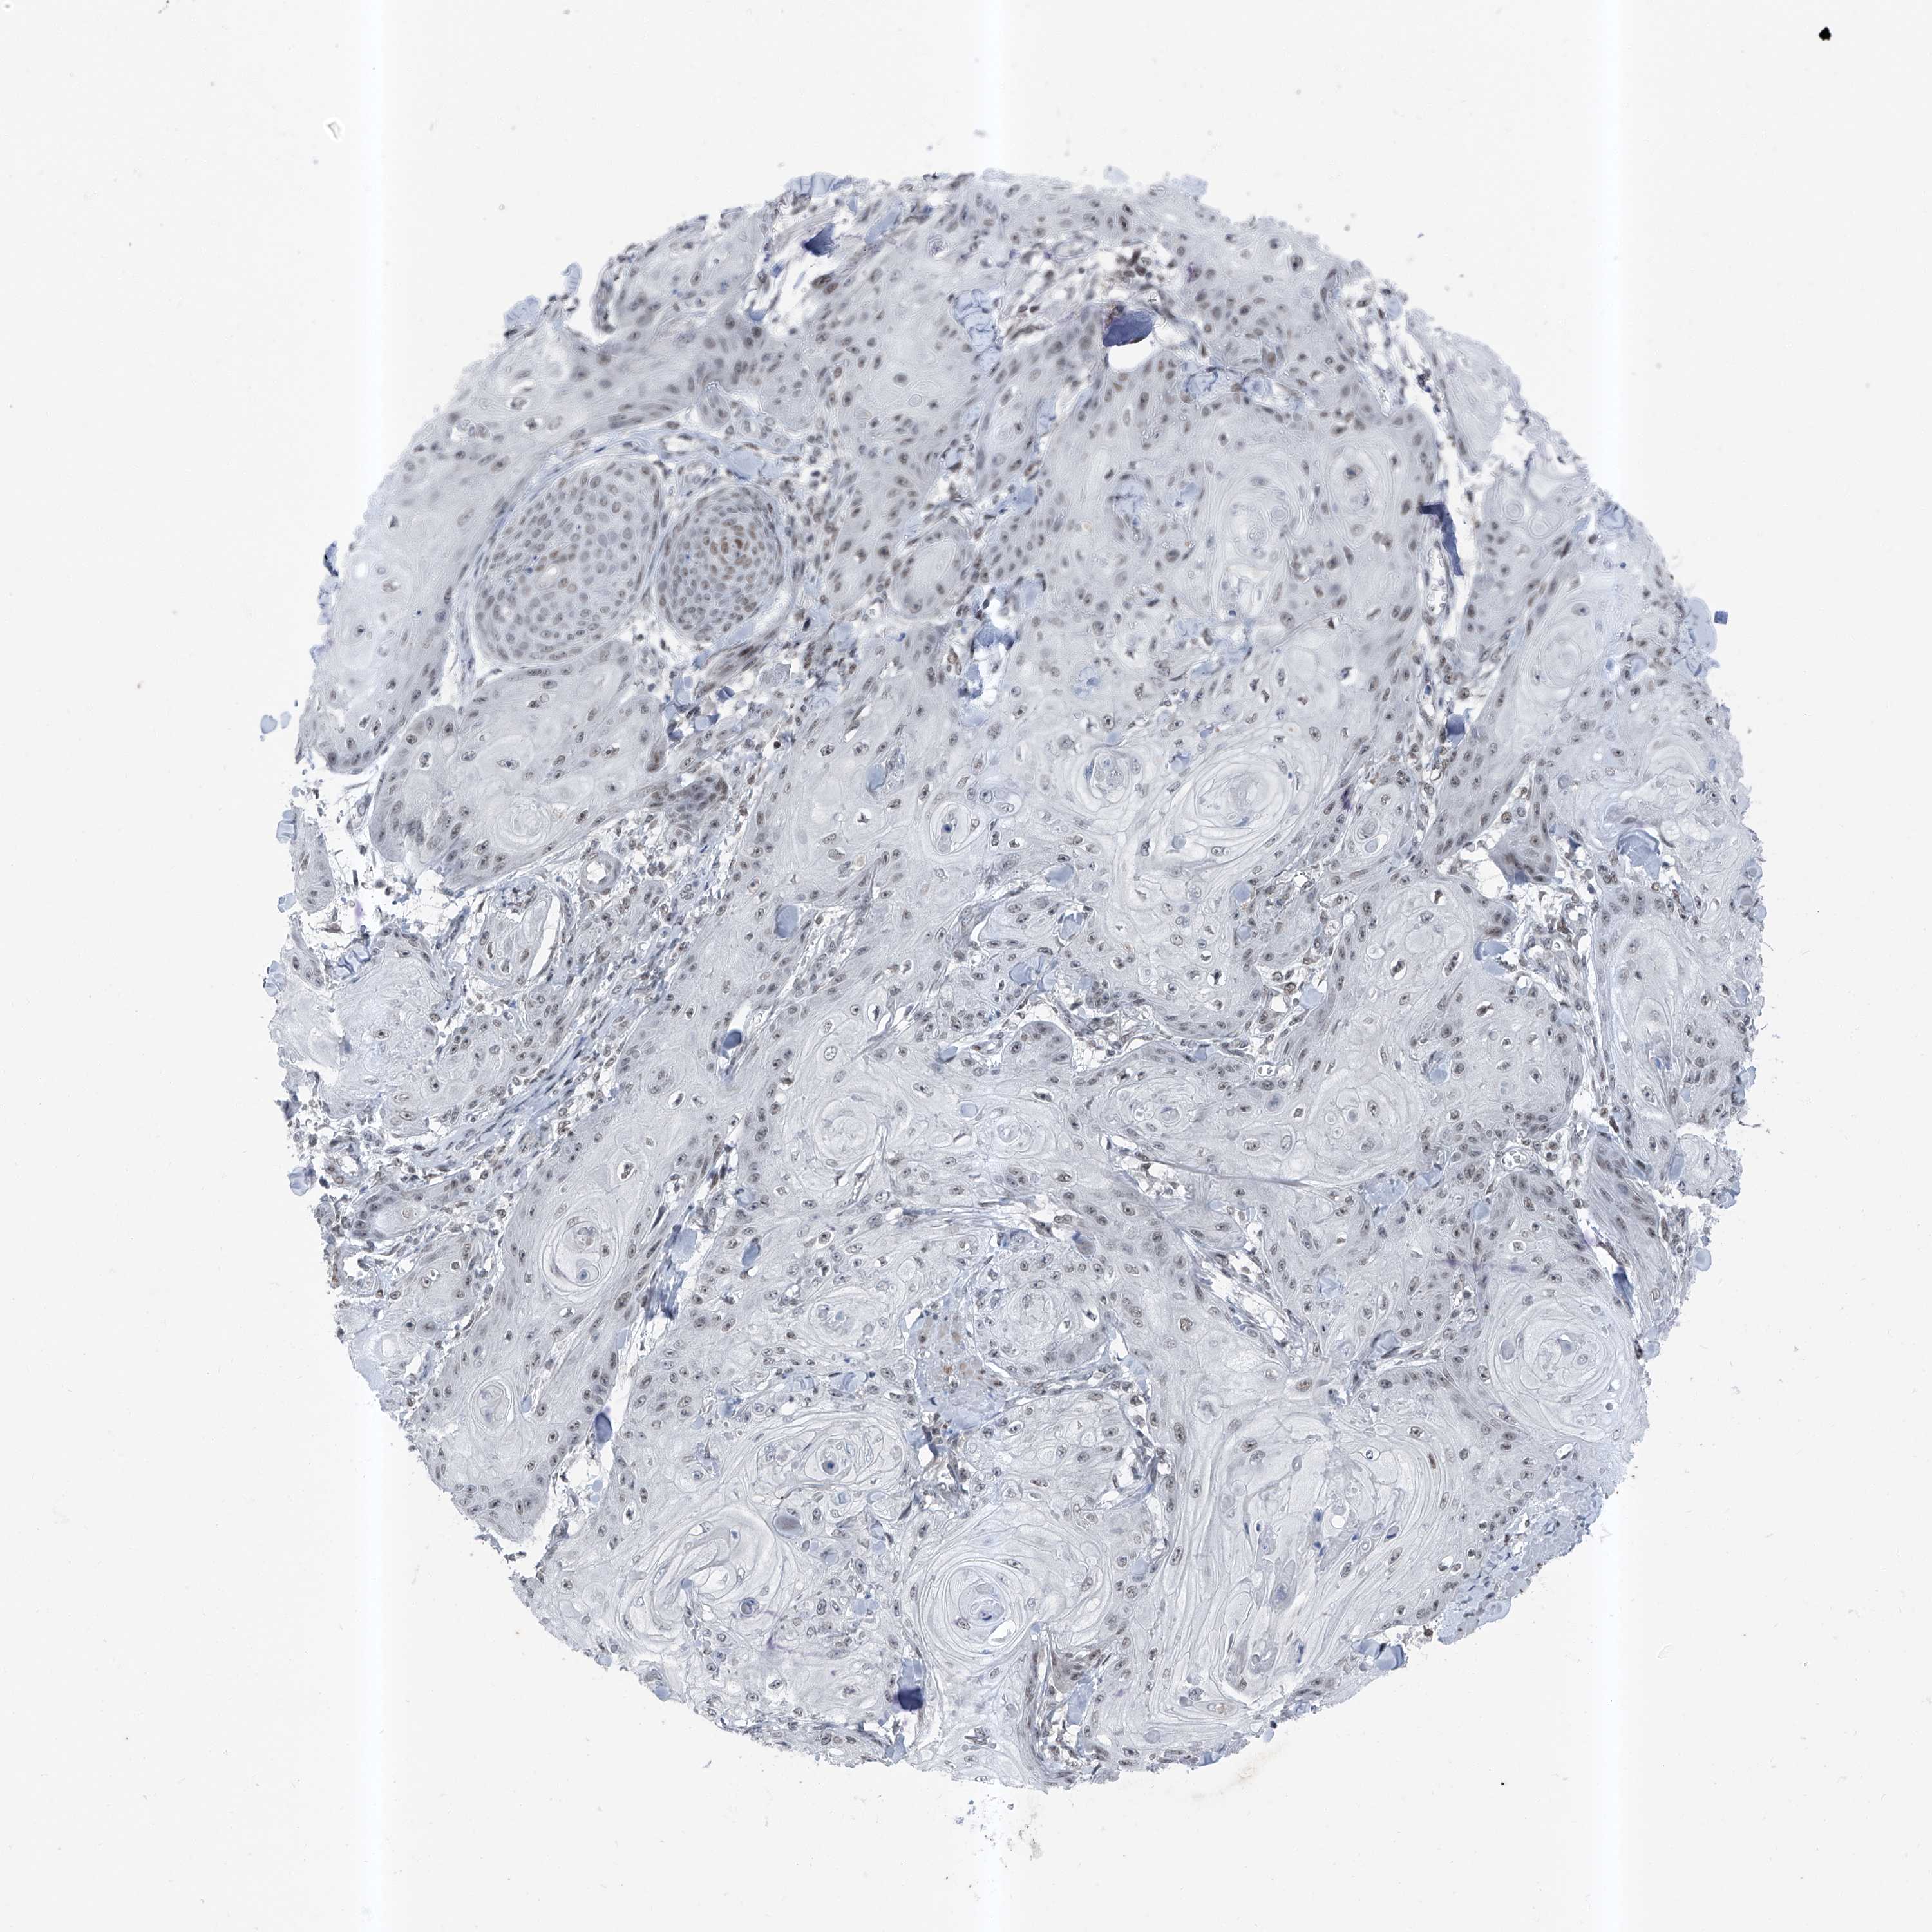

SKIN CANCER - Protein expressioni

A mouse-over function shows sample information and annotation data. Click on an image to view it in a full screen mode. Samples can be filtered based on level of antibody staining by selecting one or several of the following categories: high, medium, low and not detected. The assay and annotation is described here.

Antibody stainingi

Antibody staining in the annotated cell types in the current human tissue is reported as not detected, low, medium, or high, based on conventional immunohistochemistry profiling in selected tissues. This score is based on the combination of the staining intensity and fraction of stained cells.

Each image is clickable and will lead to virtual microscopy that enables deeper exploration of all samples and also displays staining intensity scores, fraction scores and subcellular localization as well as patient and tissue information for each sample.

Antibody HPA030472

Antibody HPA036584

Squamous cell carcinoma, metastatic, NOS